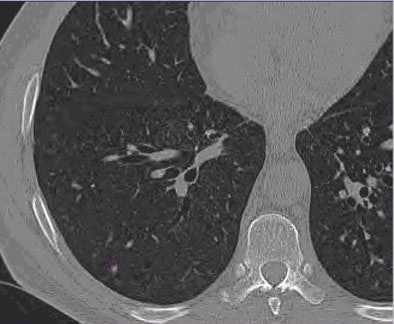

![]() |

| Images of solid lung nodules include uncompressed CT data (above), 24:1 compression (below), 48:1 compression (next down), and 96:1 compression (bottom). CAD detection performance of solid lung nodules greater than 4 mm in size did not suffer until 48:1 compression, and was found to be robust up to 96:1 even when the subjective visual appearance of the compressed images was degraded. The results suggest that 3D lossy wavelet compression can be performed without significant loss of CAD detection performance, which can minimize data storage and ultimately facilitate the implementation of CAD technology in a PACS environment. Images courtesy of Philippe Raffy, Ph.D. |